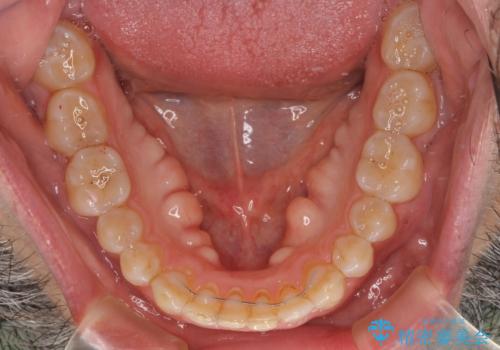

- 前歯のデコボコを気にして来院された患者様です。

インビザラインでもワイヤー装置でも対応可能でしたが、仕事の都合で来院回数を減らしたいとのことでインビザラインによる矯正治療を選択されました。

著しく咬合力が強いため、奥歯がしっかりと噛めずに治療が長引くことが懸念されました。

1セット目のインビザラインを使用した際には左右ともに大臼歯が咬み合っていなかったのですが、2セット目できっちりと仕上げることができました。